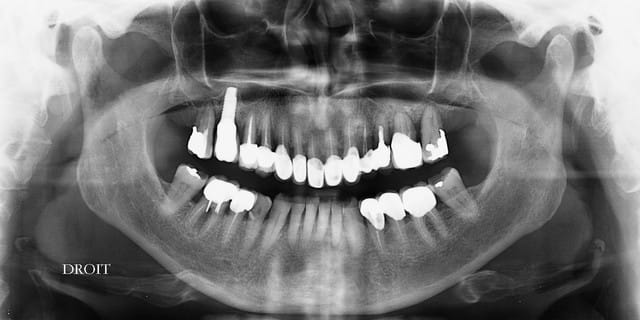

des nouvelles de ce cas, ou l'os devait disparaitre et les céramiques casser....pour le moment c'est intact, et les 3 semaines sont passées...je ne considère pas avoir gagné, mais je n'ai pas perdu non plus :-))

Se sim pano du 19.06 - Eugenol